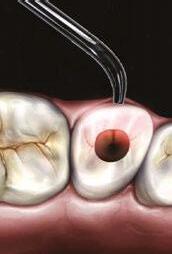

Case 1: This case was a 54-year-old male that the general dentist had initiated root canal therapy on tooth No. 31. During the procedure, a large file was separated in the mesial buccal canal. The patient was still in pain and was seen in one of our emergency appointments. The CBCT reveals that not only was the file separated around the curvature in the root, but the IAN was in direct contact with the apex of tooth No. 31. From the CBCT, the ML/MB joined so the plan was to negotiate the ML canal to length, and then, run GentleWave to allow for cleaning of the very complex anatomy that was present. I did minimal instrumentation in this case due to the other canals already having been prepared by the general dentist. I ran the GentleWave through the entire cycle without any issues; the patient was comfortable the entire time. Upon injection of sealer in the ML canal, I could see it start to come up in the MB canal revealing that it had cleaned around the file. The final obturation reveals that nothing was extruded into the IAN canal. The patient was pain free the next day when we called him